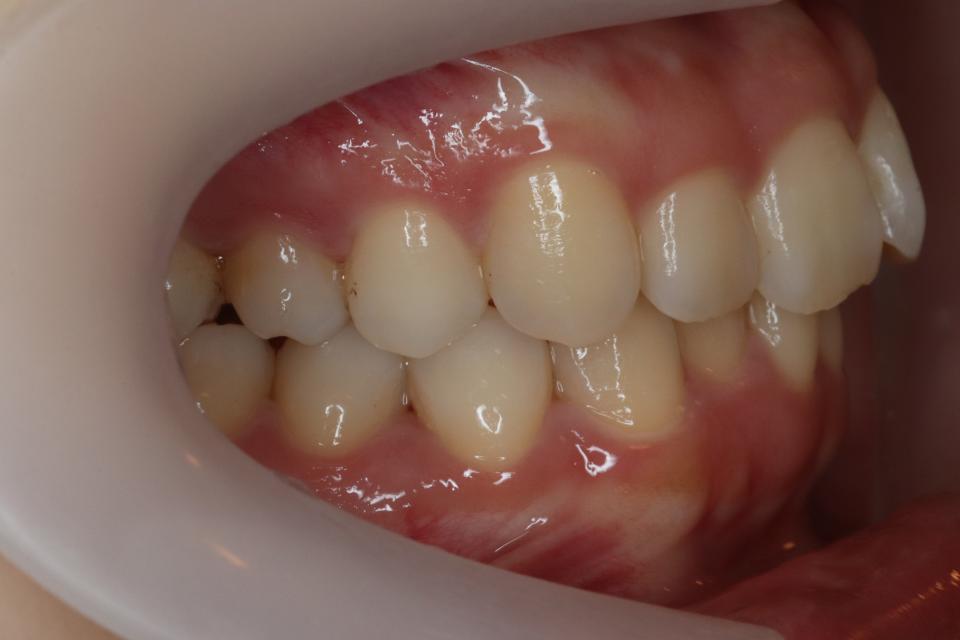

上顎前突(出っ歯)のマウスピース矯正治療例(抜歯あり)

矯正治療前

20代女性の患者さんです。

歯並びのガタガタと出っ歯気になり矯正治療を始めました。

左上4番目の歯を抜歯して、マウスピース型の矯正治療装置を使用し、歯のやすり掛け(IPR)を行いました。